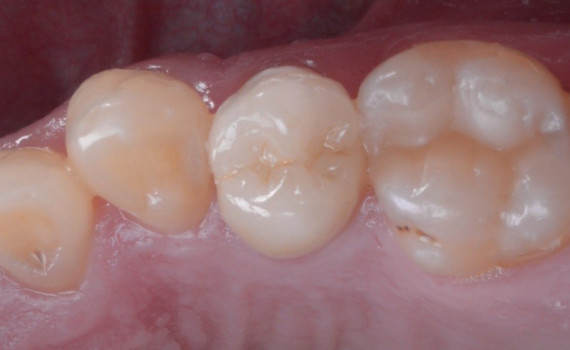

Rezultatul final ne arată cât de importată e atenția la detalii și cât de mult poate să ne schimbe un singur dinte care nu este în armonie cu restul.